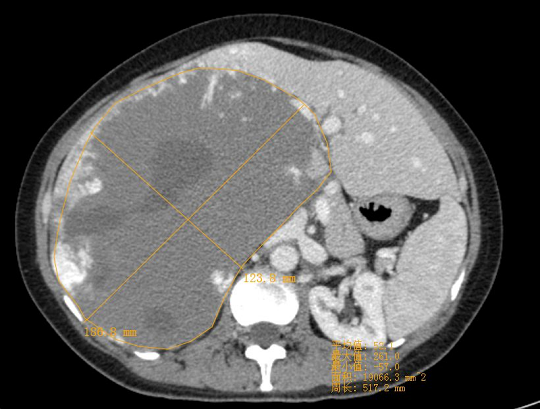

圖為患者肝巨大血管瘤的影像資料。